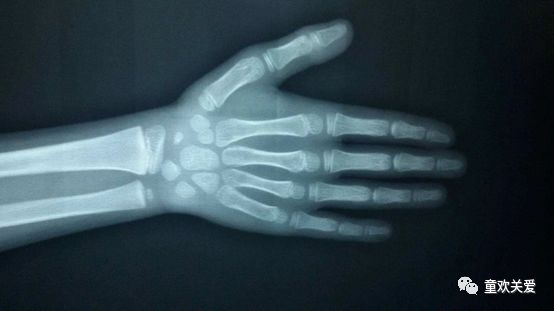

很多父母都认为测骨龄是一个较为麻烦的事情,其实只需配合完成一次左侧腕关节正位X线光片拍摄即可。

1)标准骨龄片的拍摄方法

- 左手自然张开,手心向下,中指与前臂保持在同一条直线

- 球管对准第三掌骨头,管片距约为80cm

- 投照范围包括:全部手指、掌部及腕关节以上3-5cm